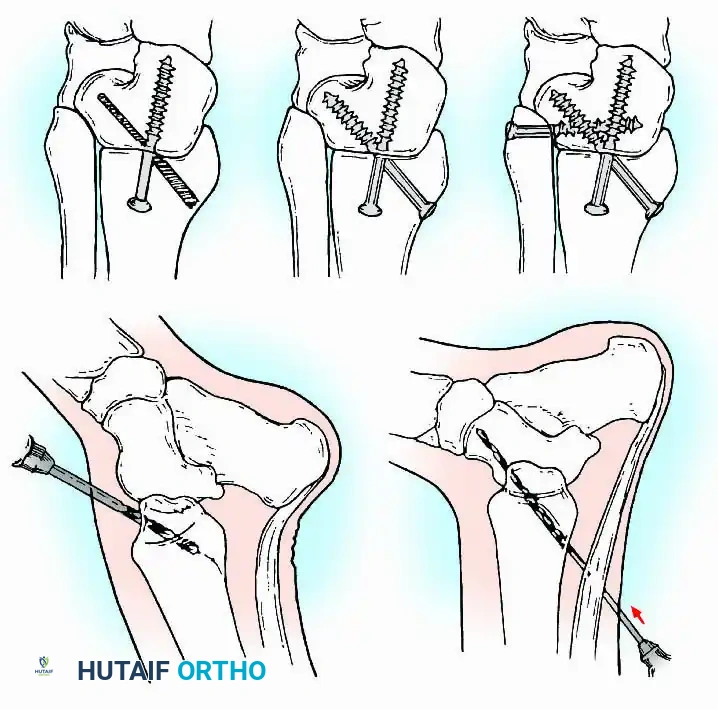

External Fixation

Historically pioneered by Charnley, external compression arthrodesis utilizes pins placed through the distal tibia and the body of the talus. Because Charnley's original uniplanar device lacked rotatory stability, Calandruccio designed a triangular frame to control motion in all three planes while applying massive compression.

Modern iterations, such as the Calandruccio II compression device, offer greater latitude in pin placement to avoid compromised skin. Ring or circular external fixators (Ilizarov, Taylor Spatial Frame) are the gold standard for salvage situations, including active infection, massive bone loss, or failed TAA, as they allow for simultaneous compression, deformity correction, and early weight-bearing.

Internal fixation is currently the preferred method for uncomplicated ankle arthrodesis due to higher union rates, superior patient comfort, and the elimination of pin-tract infections. Biomechanical studies demonstrate that crossed, large-diameter (6.5 mm or 7.3 mm) cannulated cancellous screws provide exceptional resistance to shear and torsional forces.

A standard construct involves two or three screws:

1. A "home run" screw directed from the posterior malleolus into the anterior neck of the talus.

2. A screw from the medial malleolus into the lateral body of the talus.

3. A screw from the anterolateral tibia into the medial talar body.

In cases of severe osteopenia or when extending the fusion to the subtalar joint (Tibiotalocalcaneal Arthrodesis), retrograde intramedullary nailing provides a load-sharing construct with superior bending stiffness.